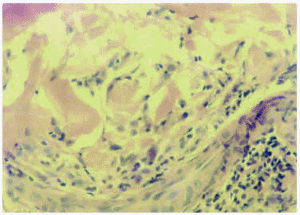

Se realizaron biopsias cutáneas de los 5 casos clínicos con tinciones para hematoxilina-eosina, mucina (hierro coloidal) y fibras elásticas (iodina de Verhoeff). En todos los casos se apreciaba una epidermis relativamente normal. En la dermis papilar y media presentaban un infiltrado inflamatorio granulomatoso denso y difuso, compuesto por células gigantes multinucleadas que contenían un material basófilo y algunos histiocitos acompañados a veces de linfocitos (figs. 3 y 4). En los casos 1, 3 y 4 se asociaban dichos cambios a un infiltrado inflamatorio compuesto por linfocitos pequeños, mientras que en el caso 2 este infiltrado inflamatorio era muy notable y en el caso 5 era escaso. No se apreciaban histiocitos «en empalizada» y las tinciones para mucina no mostraron cambios degenerativos en el colágeno ni incremento de mucina en las zonas con infiltrado granulomatoso. En las tinciones para fibras elásticas se apreciaban células gigantes multinucleadas que envolvían las fibras elásticas o con dichas fibras dentro de su citoplasma (fig. 5). En las áreas correspondientes al centro de la lesión anular, no se observaban fibras elásticas. En la parte más externa de la lesión cutánea se apreciaba elastosis actínica, con conglomerados de material basofílico en la dermis papilar.

Fig. 5.--Pérdida de fibras elásticas en la zona de inflamación granulomatosa. (Tinción para fibras elásticas, x40.)